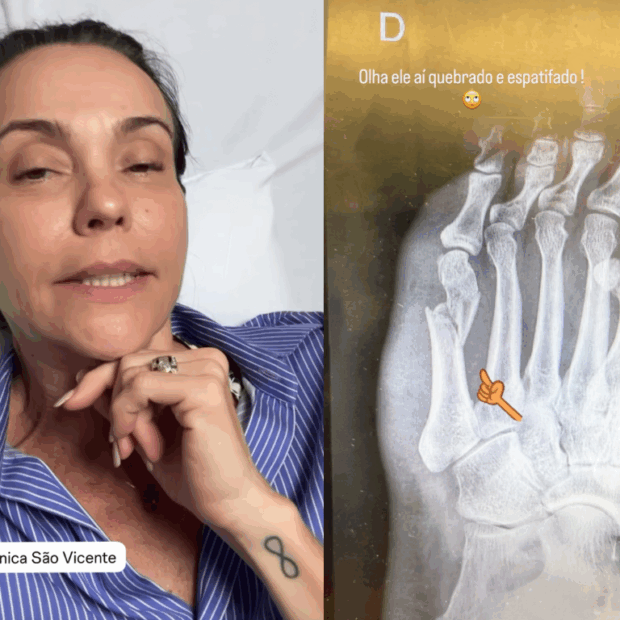

A Sophia estava de cabeça pra baixo no sofá, a atriz foi brincar com ela tentando fazer uma parada de mão, o cachorro pulou, derrubou as duas no chão, e o resultado foi o quinto metatarso do pé quebrado e espatifado. Operação marcada pra quinta, alta prevista pra sexta com plaquinha de metal instalada.

O que fez esse caso virar assunto foi a própria Flávia, que foi ao Stories com uma honestidade desarmante e disse a frase que todo mundo de 50 anos já pensou sobre si mesmo pelo menos uma vez: “A pessoa tem 53 anos e pensa que tem 20, e brinca, pula e vira de cabeça pra baixo com a filha.” Ela riu de si, entregou o contexto completo e ainda batizou o acidente de “brincadeira idiota”, sem deixar margem pra nenhuma outra interpretação.